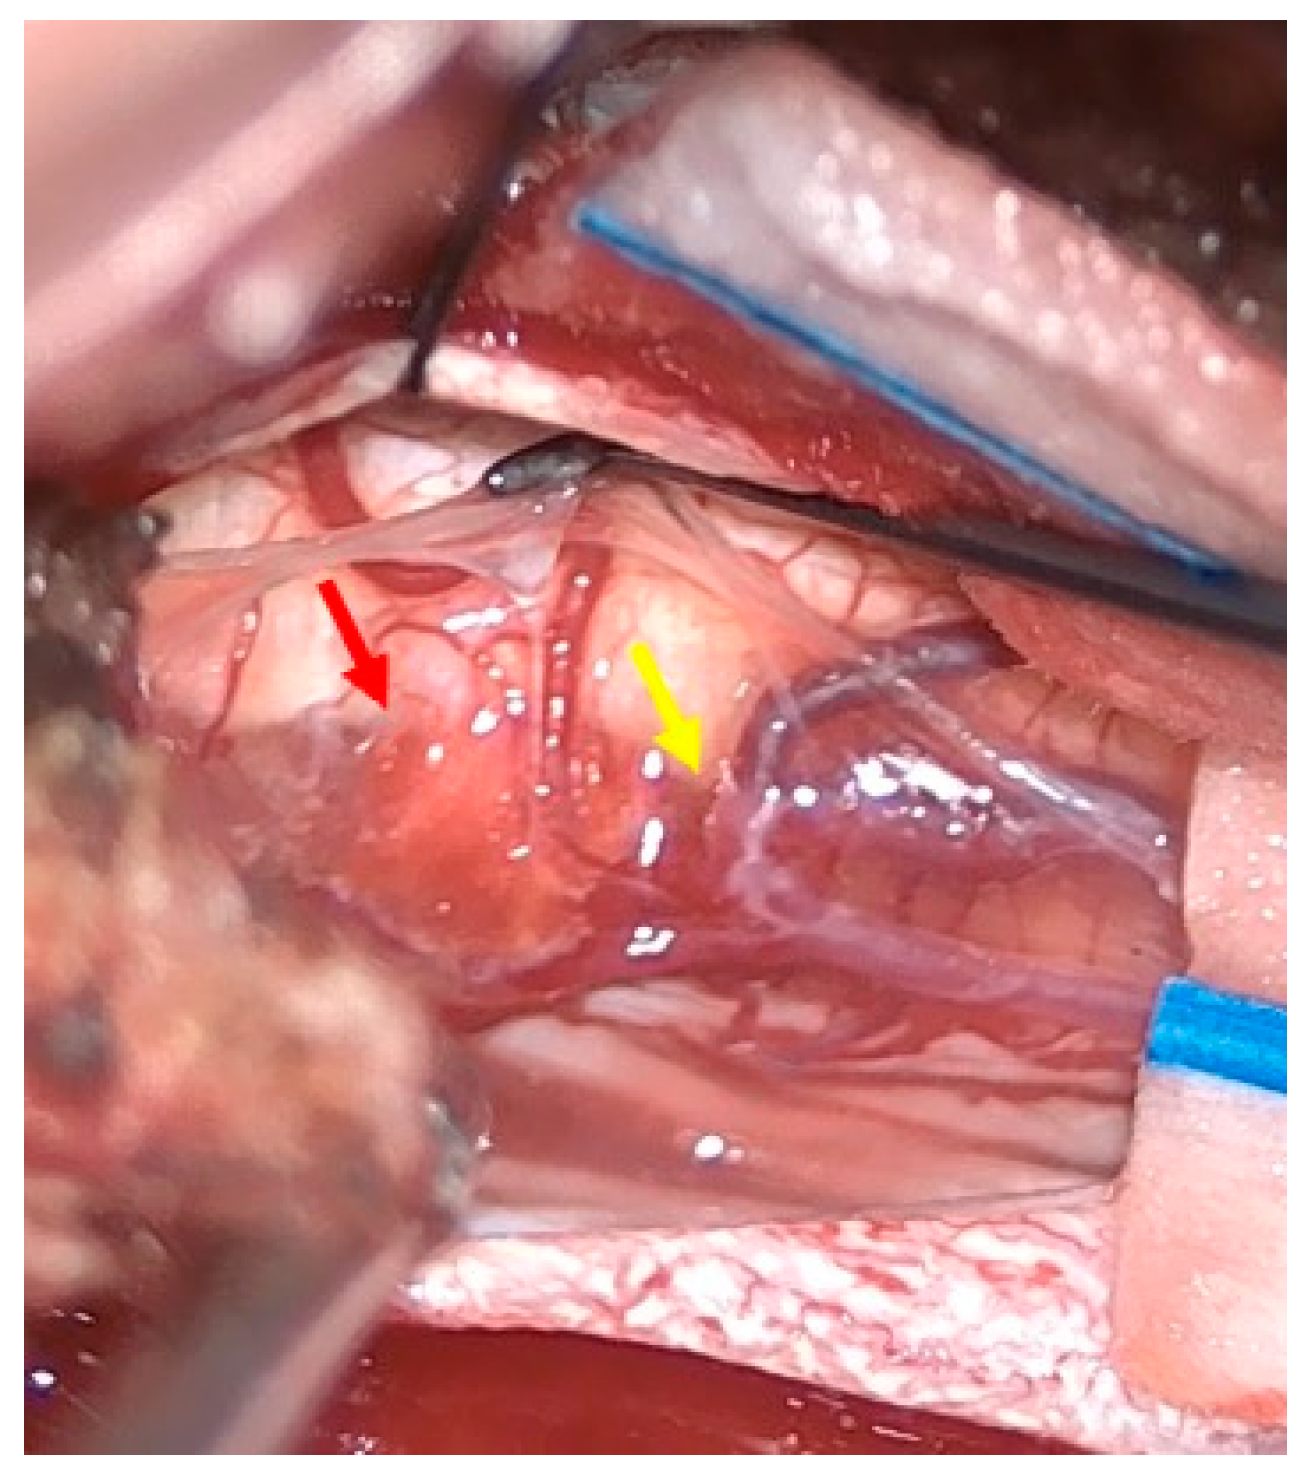

Figure 1.

MRI of the thoracic spine. Left: T1-weighted image showing the expansive lesion at the T11 level (red arrow). Right: T2-weighted image revealing the lesion with surrounding edema (yellow arrow).